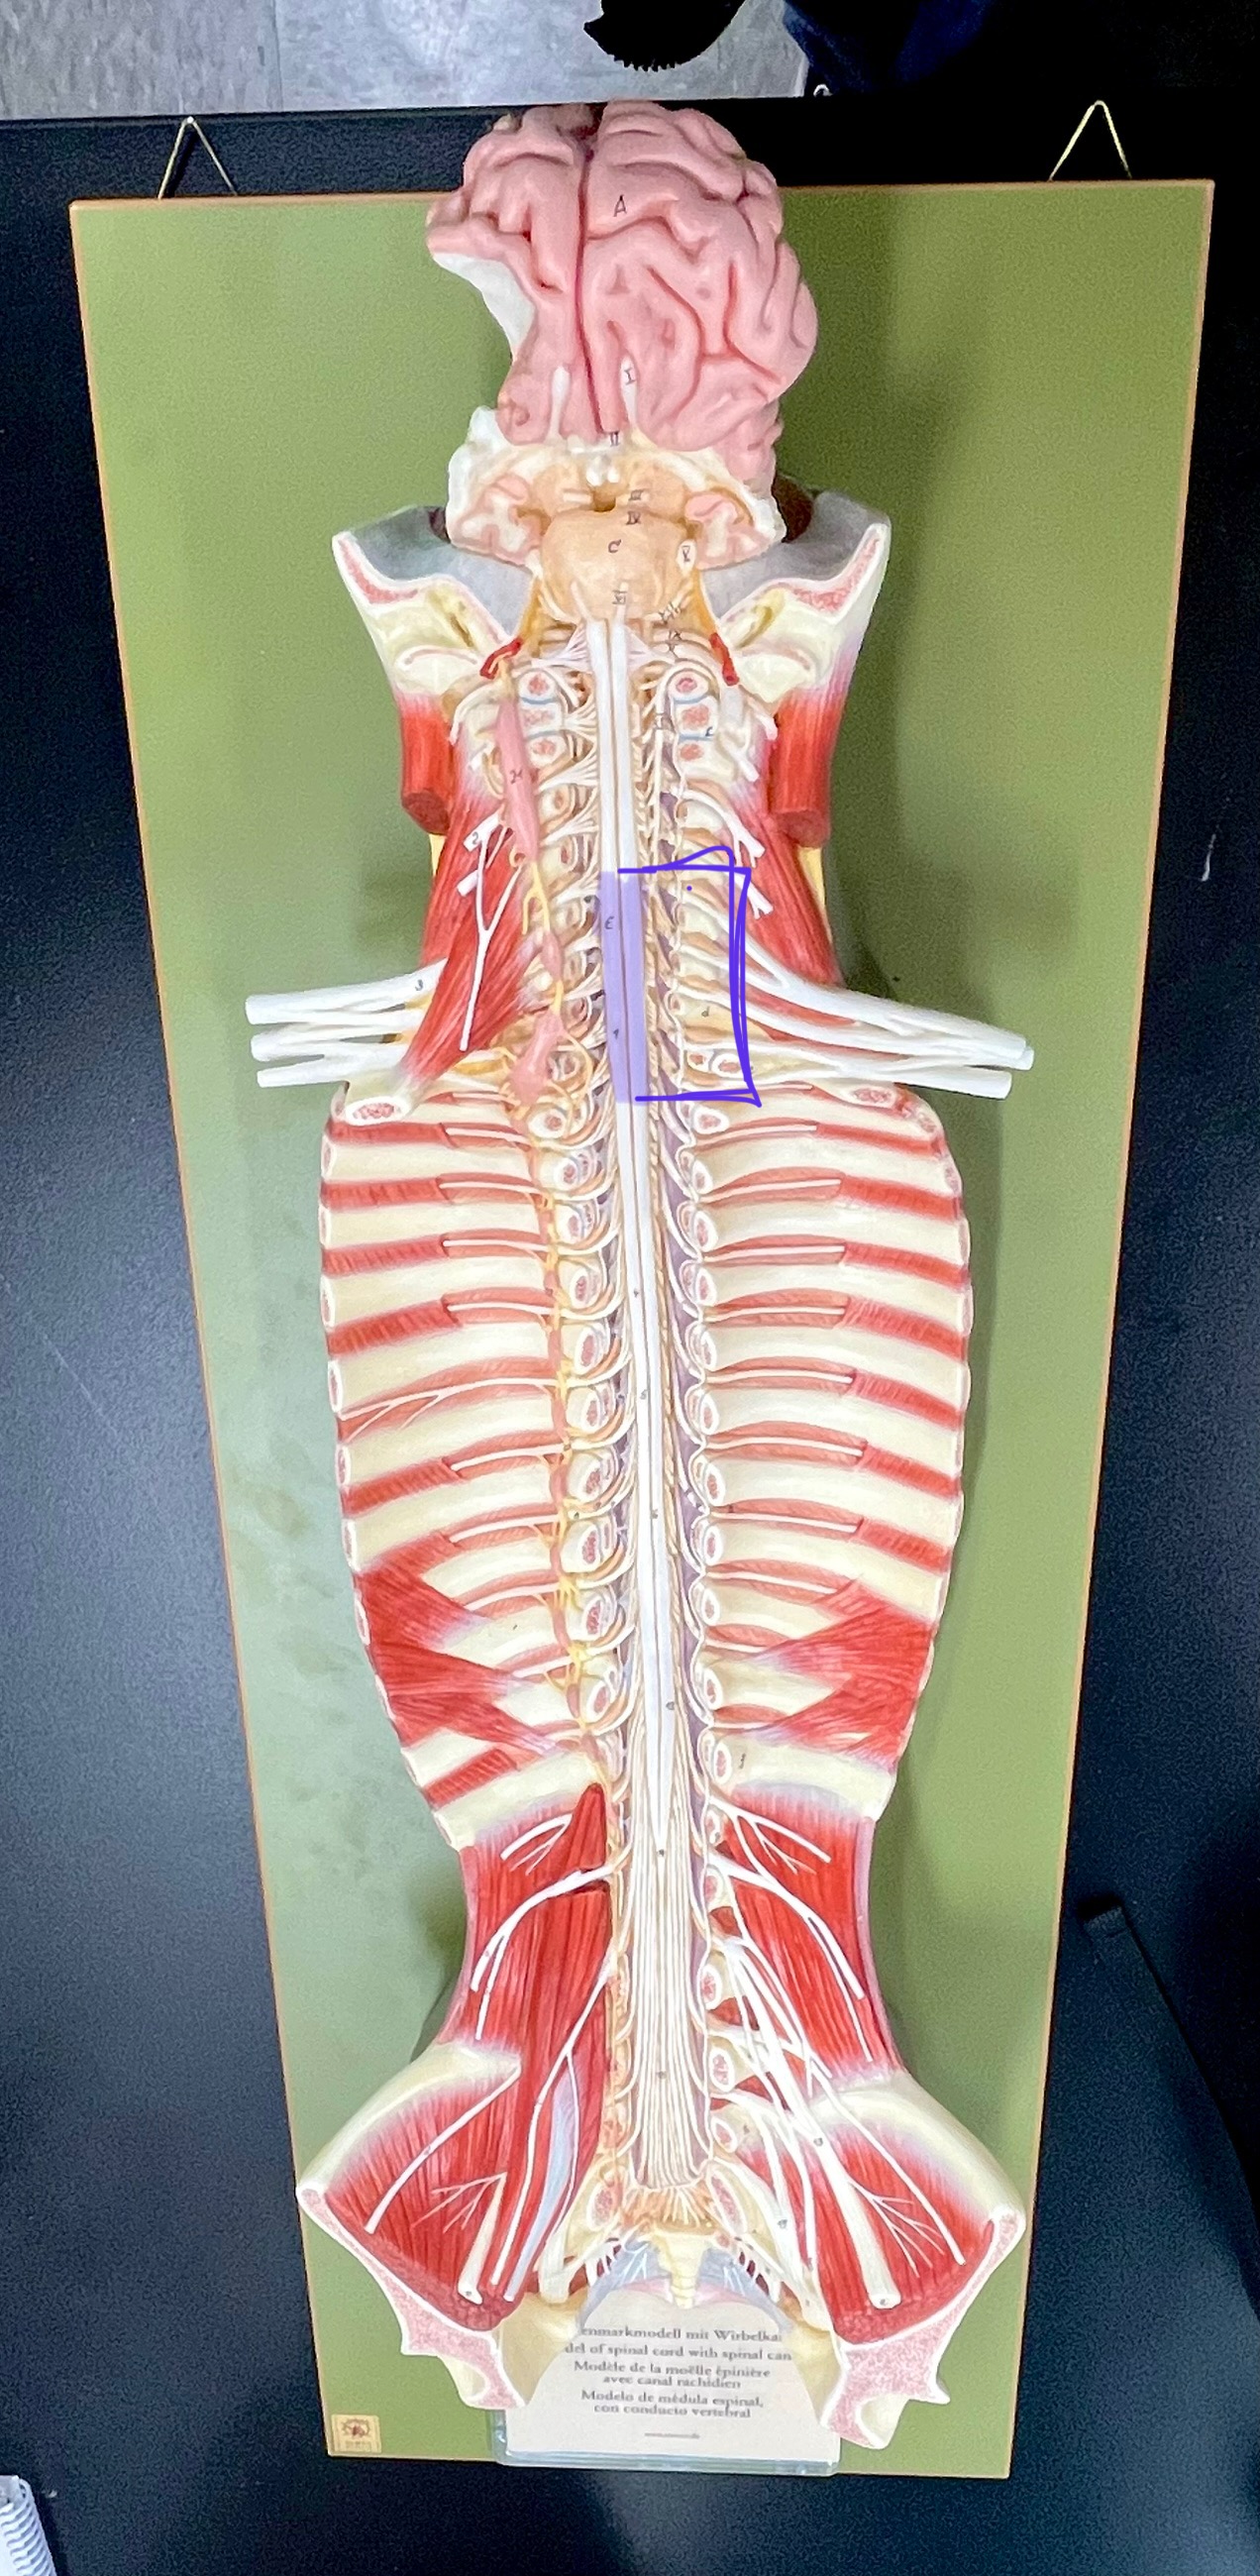

What type of spinal nerve is this? How many pairs?

cervical (8 pairs)

What type of spinal nerve is this? How many pairs?

thoracic (12 pairs)

What type of spinal nerve is this? How many pairs?

lumbar (5 pairs)

What type of spinal nerve is this? How many pairs?

sacral (5 pairs)

What type of spinal nerve is this? How many pairs? (not pictured)

coccygeal (1 pair)

epidural space

dura mater

subdural space

arachnoid mater

subarachnoid space

pia mater

denticulate ligaments

cervical enlargement

cervical enlargement

thoracic segment

lumbar enlargement

lumbar enlargement

conus medullaris

conus medullaris

filum terminale

cauda equina

sympathetic chain ganglia